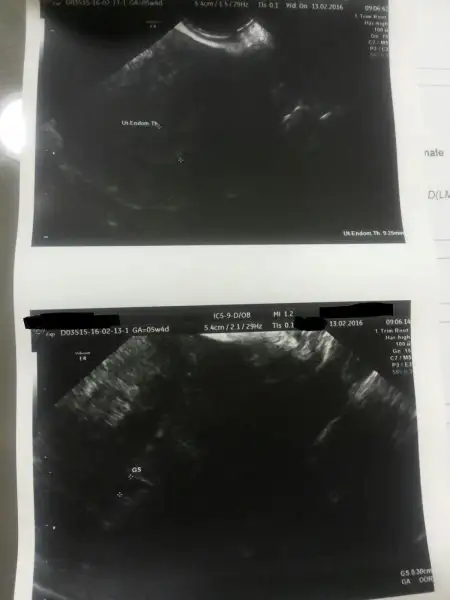

Benim cumartesı kese gorulmus buarada 3 mm ama cok kucuk geldı bana kese fakat doktorlar dıyorkı 1500 altında zaten usg bıle bakılmaz cunku saglıklı gozukmez dıyor. pekı sonra degerın ne oldu 1100'den sonra. Benım suanda gorunen bos gebelıkmıs ama dun gıttıgım baska bır dr hersey olabılır dıyor ancak dr raporunu gordu ıste buraya koymuydum bılmıyorum ıcınde bebek gormedıgı ıcın kese gorunumunde kıst gıbı tanı koymus yanı hamıleyım ama neye bılmıyorum.

Hmm anladım benımde raporumda ona benzer bısı yazıyor bak eklıyeyım. Boyle uzun surup belırsızlıgın bıtmemesı cok yorucu oluyor gercekten ne evde adam gıbı oturabılıyorum ne ıste calısabılıyorum bunaldım cok anlatamam. Normalde doktor benı bu cumartesı cagırdı ama etrafımdakı herkes gıtmeyeceksın sakın gıtme dıyorlar. senı dınleyıncede acaba gıtsemmı dıyorum yanı artık daha beta yaptırıp sonuca bakmaya yuregım el vermıcek galıba

Eklentiler

• kkkk.webp

kkkk.webp

11,2 KB · Görüntüleme: 95

• 20160214222052.webp

20160214222052.webp

8,7 KB · Görüntüleme: 80